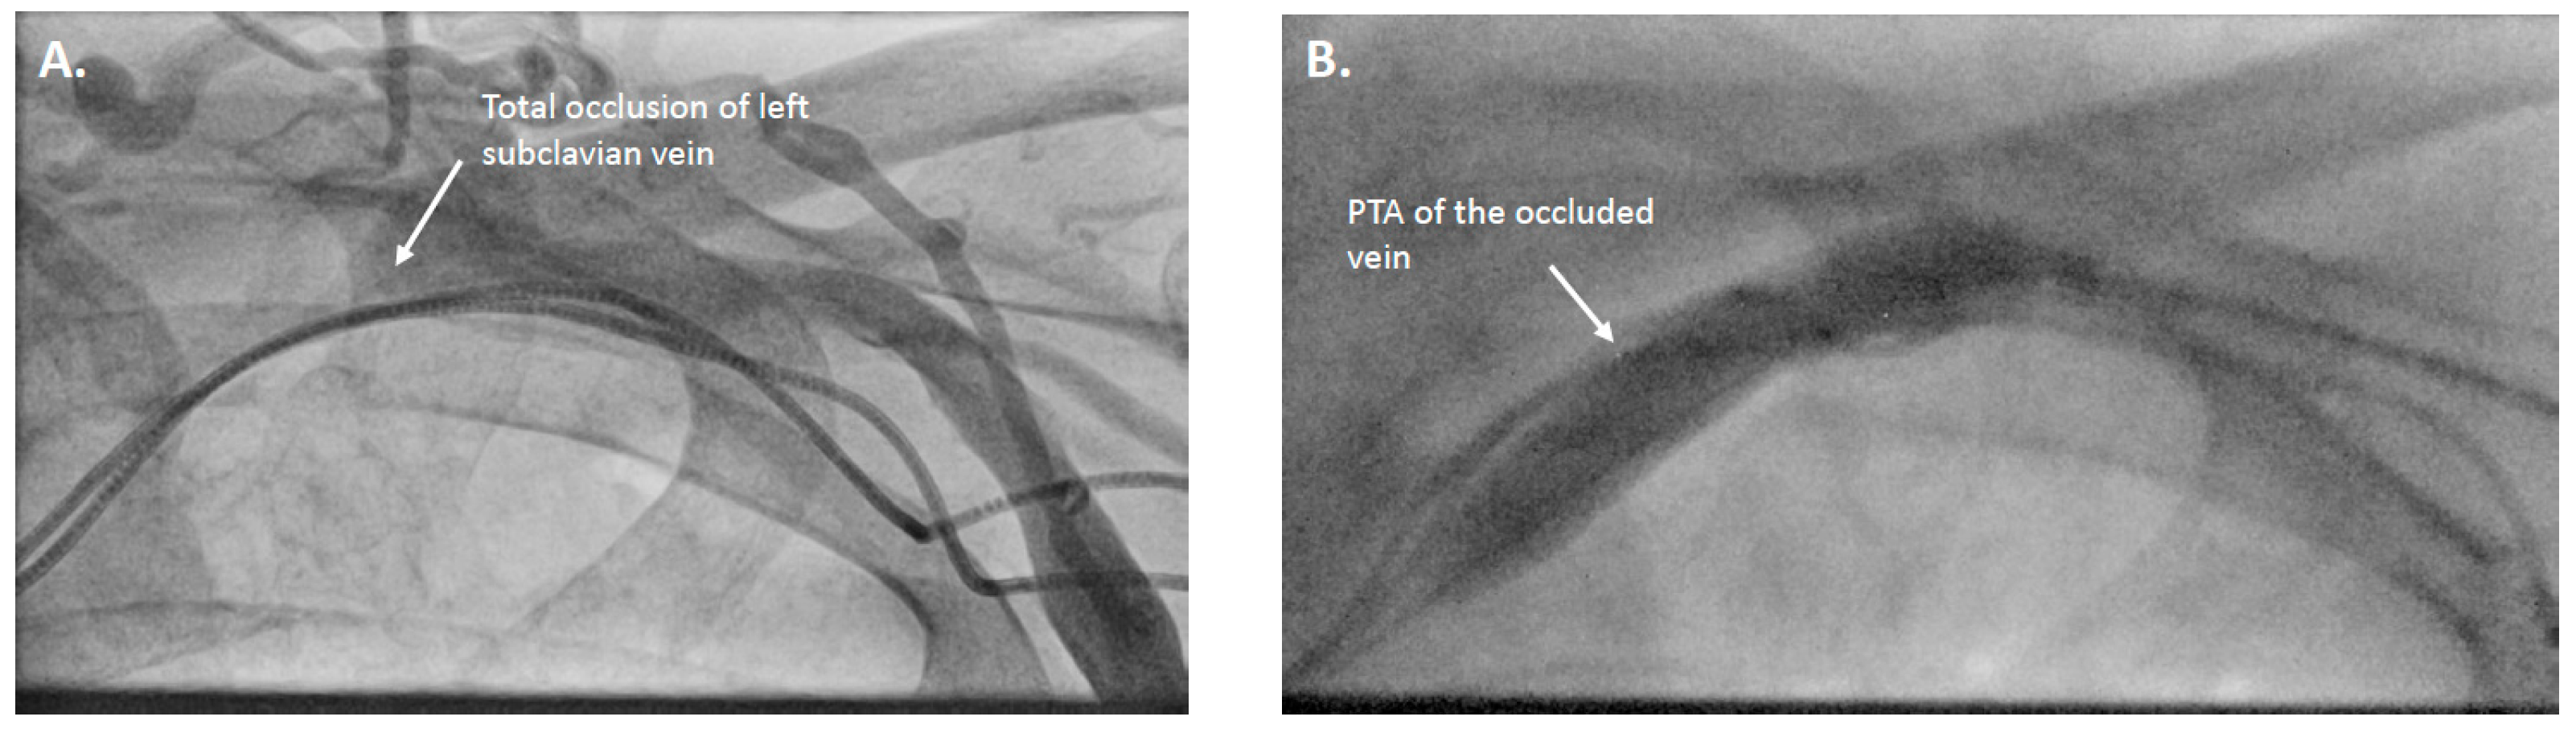

| 3 | 2-chamber pacemaker → CRT upgrade | HFmrEF, increased ventricular pacing | Left subclavian vein occlusion | Recanalization and PTA via axillary/brachial vein | Reocclusion next day |

| 8 | Dual-chamber pacemaker → CRT-P upgrade | LVEF deterioration, increased ventricular pacing | Left subclavian vein occlusion | Recanalization and PTA via lateral left subclavian vein | CRT-P upgrade successful |